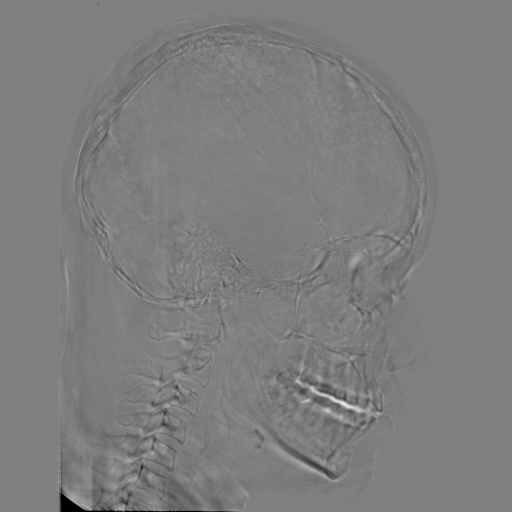

5.2 Head Data

Refer to caption

(a) Reference

(b) 0superscript00^{\circ} perspective

(c) (b)-(a)

7.80, 0.9093

Pix2pixGAN Prediction

(d) 0superscript00^{\circ} Cartesian

(e) 0&180superscript0superscript1800^{\circ}\&180^{\circ} Cartesian

(f) 0&180superscript0superscript1800^{\circ}\&180^{\circ} polar

6.06, 0.9249

2.99, 0.9820

2.07, 0.9842

Pix2pixGAN difference

(g) (d)-(a)

(h) (e)-(a)

(i) (f)-(a)

TransU-Net Prediction

(j) 0superscript00^{\circ} Cartesian

(k) 0&180superscript0superscript1800^{\circ}\&180^{\circ} Cartesian

(l) 0&180superscript0superscript1800^{\circ}\&180^{\circ} polar

6.45, 0.9356

2.36, 0.9864

3.65, 0.9734

TransU-Net Difference

(m) (j)-(a)

(n) (k)-(a)

(o) (l)-(a)

Figure 11: Perspective deformation learning in one exemplary patient case for cephalometric imaging. In (b), the left and right sides of the mandible do not overlap well, as indicated by the arrow. In (c), a scale bar of 2 mm is displayed (zoom in for better visualization), as 2 mm is the clinically acceptable precision for cephalometric landmark detection. In (e), (h) and (j), incorrect areas are marked by the red arrows.

The results of one exemplary patient for cephalometric imaging are displayed in Fig. 11. In the 0superscript00^{\circ} perspective projection image (Fig. 11(b)), because of perspective deformation, anatomical structures from the left and right sides do not overlap well, especially for the mandible as indicated by the red arrow in Fig. 11(b). It causes inaccuracy in determining the cephalometric landmark of the gonion. The difference of Fig. 11(b) to the reference Fig. 11(a) is displayed in Fig. 11(c). A scale bar of 2 mm is displayed in Fig. 11(c), as 2 mm is the clinically acceptable precision for cephalometric landmark detection. It is obvious that many anatomical structures in the 0superscript00^{\circ} perspective projection images have position shifts larger than 2 mm. In the prediction image (Fig. 11(d)) using a single 0superscript00^{\circ} view in Cartesian coordinates, perspective deformation is reduced to some degree, as displayed in the difference image Fig. 11(g). For example, the mandible region has less error. However, Fig. 11(g) also indicates that many bony structures still have deviations larger than 2 mm. The results of learning from dual complementary views in Cartesian and polar coordinates are displayed in Fig. 11(e) and Fig. 11(f), respectively. Both images have little perspective deformation, as revealed by their difference images in Fig. 11(h) and Fig. 11(i). Nevertheless, in Fig. 11(e), two dark regions are indicated by the two arrows, which are better visualized in the difference image Fig. 11(h). The results of TransU-Net are displayed in Figs. 11(j)-(o). In Fig. 11(m), the structures near the porion landmark are distorted, for example, the ear canal indicated by the arrow. Consistent with Pix2pixGAN, perspective deformation is largely reduced in the both TransU-Net prediction images using dual complementary views in Cartesian and polar coordinates.